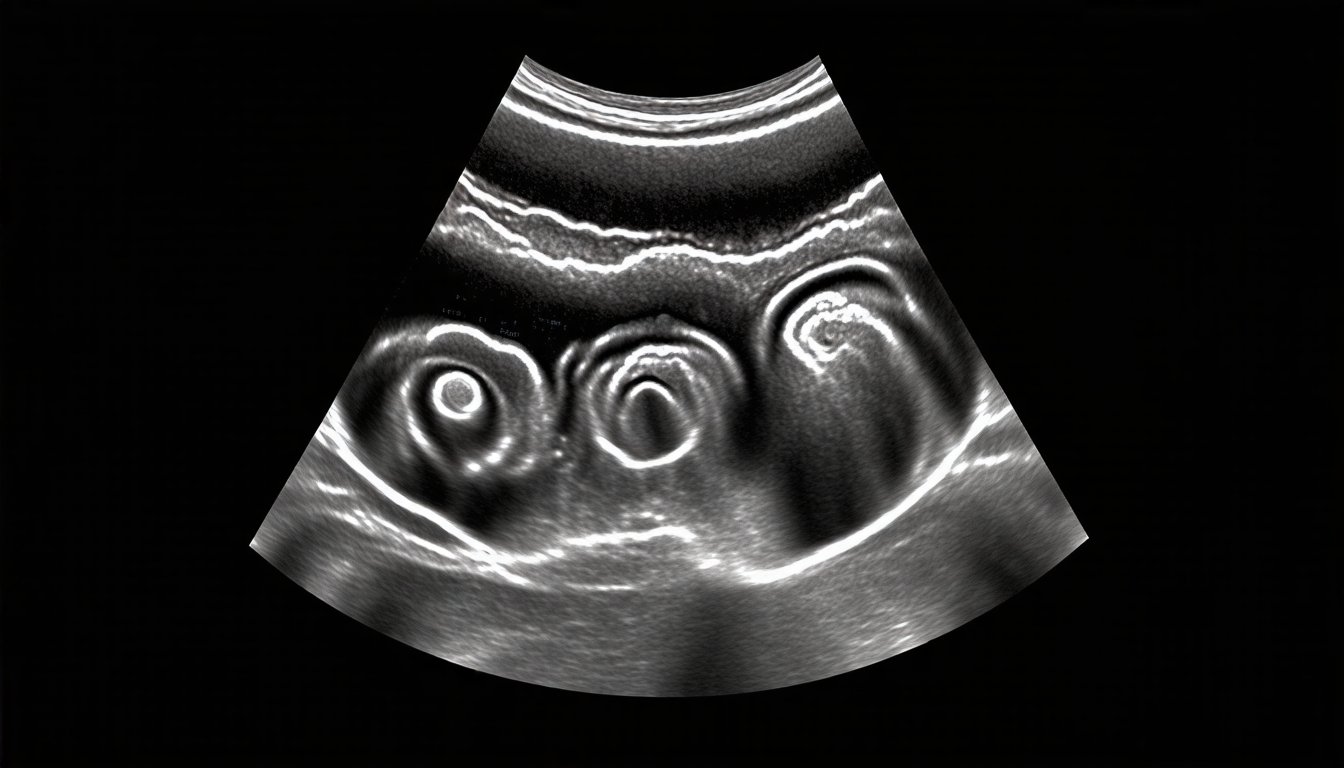

Researchers have been experimenting with deep learning techniques to detect breast cancer using ultrasound images. In a recent study, a team of scientists from Varendra University in Bangladesh trained three deep learning models – ResNet50, MobileNet, and VGG16 – on a dataset of 9,248 ultrasound images labeled as benign, malignant, or normal.

Despite these challenges, the potential benefits of AI-powered breast cancer detection make it an exciting area of research. By combining machine learning with ultrasound imaging, scientists may be able to develop a more accurate and efficient way to detect breast cancer – potentially saving thousands of lives each year.